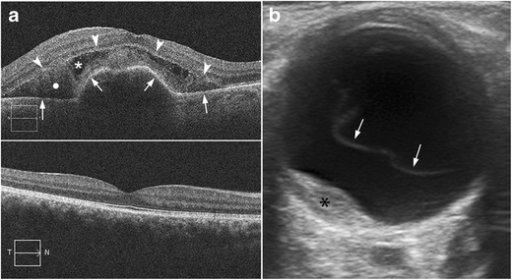

진단 (Diagnosis)

- B-scan US: 유리체출혈로 안저 관찰 불가 시

- OCT: Vitreomacular interface 평가 (VMT, MH 동반 확인)